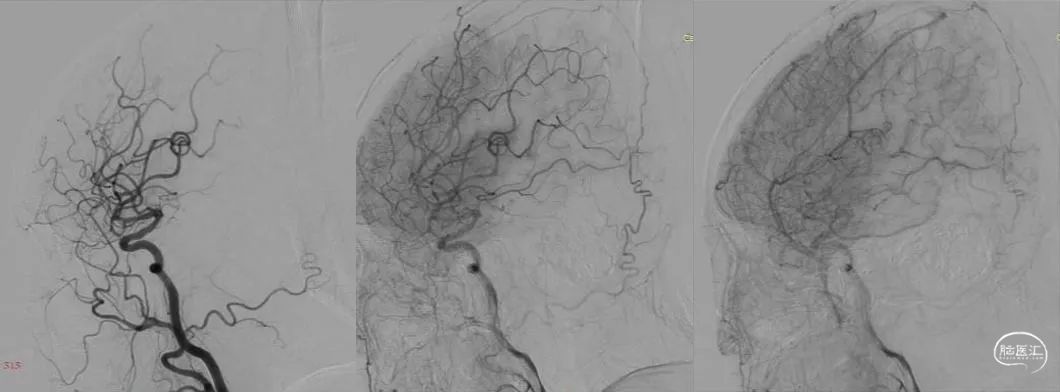

原因:支架内急性血栓形成?或是栓子脱落?立即造影复查,左侧颈动脉支架内通畅,左侧大脑中动脉、大脑前动脉主干血管、分支血管显影正常(图3)。

图3:复查造影(时间10点35分)

17点30分,患者病情突然加重,出现混合性失语,右侧肢体肌力0级,NIHSS 17分。复查头颅CT:

左侧大脑半球脑回肿胀

没有颅内出血,急诊复查造影,左侧颈动脉支架内通畅,左侧前循环颅内动脉显影良好,再次除外急性脑梗死,给与静脉乌拉地尔控制血压、甘露醇脱水降颅压治疗后,患者病情稍有缓解,NIHSS 12分,同时查灌注成像(图5)、TCCD(图6)未提示术后高灌注表现。

图5:DSA下行脑灌注检查(到达时间、达峰时间)双侧无明显差异

图6:复查造影时行TCD检查